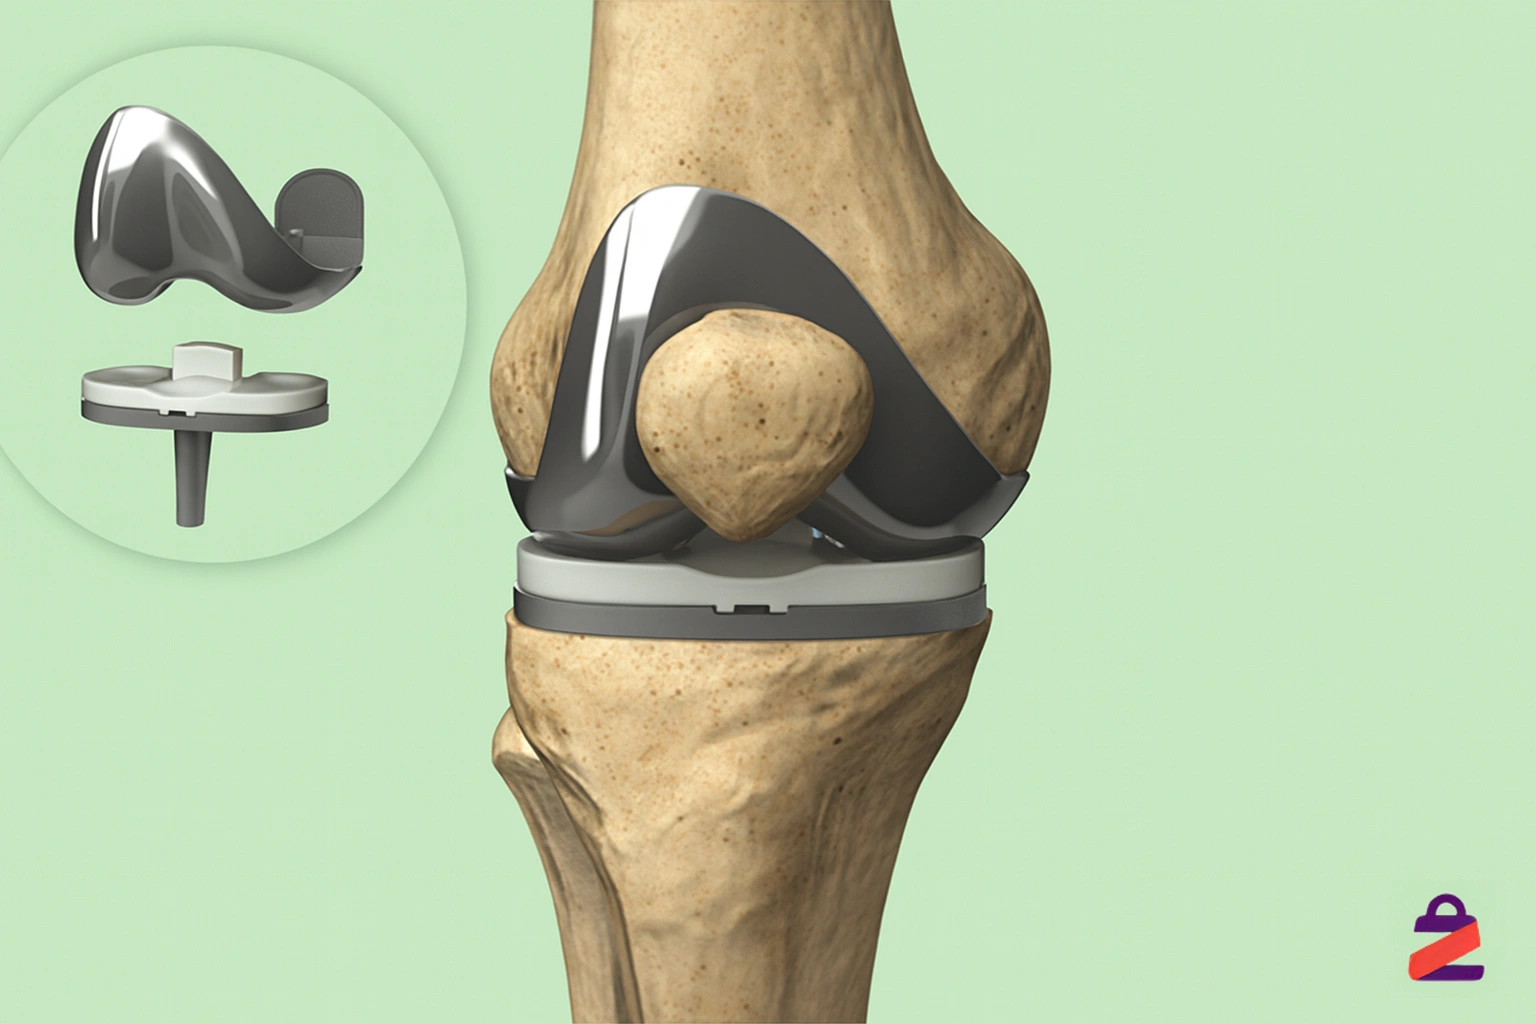

سپس بخشهای فرسودهی استخوان ران و استخوان درشتنی که سطح مفصل را تشکیل میدهند، با ابزارهای دقیق تراش داده میشوند تا سطحی یکنواخت و آماده برای قرار دادن قطعات مصنوعی ایجاد شود. در صورت نیاز، سطح زیر کشکک هم تراش داده میشود و با یک قطعه پلاستیکی جایگزین میشود.

بعد اجزای مفصل مصنوعی که معمولاً از فلز (مثل تیتانیوم یا آلیاژ کبالت-کروم) و پلاستیک فشرده ساخته شدهاند، با دقت روی استخوانها نصب میشوند.

این قطعات ممکن است با چسب مخصوص استخوانی در محل خود ثابت شوند. جراح پس از اطمینان از تراز بودن و حرکت روان مفصل، برش را بخیه زده و زانو پانسمان میشود.